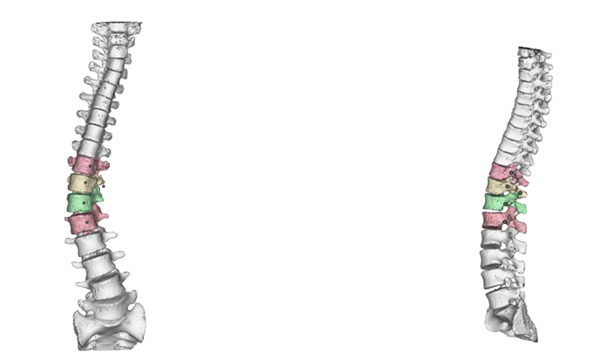

A subtype of powder bed fusion, LPBF uses a metal powder bed and one or more (up to 12) high-power lasers. LPBF 3D printers use lasers to selectively fuse metal powders layer by layer on a molecular basis until the pattern is complete. LPBF is a high-precision 3D printing method commonly used to create complex metal parts for aerospace, medical and industrial applications.

EBM, also known as electron beam powder bed fusion (EB PBF), is a metal 3D printing method similar to LPBF, but uses an electron beam instead of a laser fiber. This technology is used to make parts such as titanium orthopedic implants, jet engine turbine blades and copper coils.